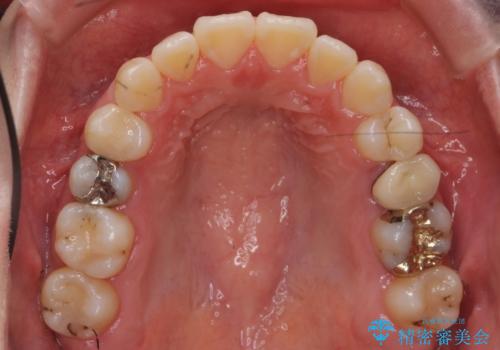

下の小臼歯を抜歯しましたが、その代わり下の親知らずを残して咬ませたので、歯の数は変わっていません。

ただし、左下の親知らずを残すには厚みのある歯ぐきを処置しています。(ディスタルウェッジ)

左上奥歯は、矯正後セラミックインレー修復を行なっています。

- 118万円(矯正治療:90万円 通院費、クリアリテーナー代込み、左下8:歯周外科処置 サービス 左上5:ファイバーコア 2万円、仮歯1万円、メタルボンドクラウン9万円、左上6:PGAインレー6万円 右上4:emaxインレー7万円)費用は治療当時の料金となります